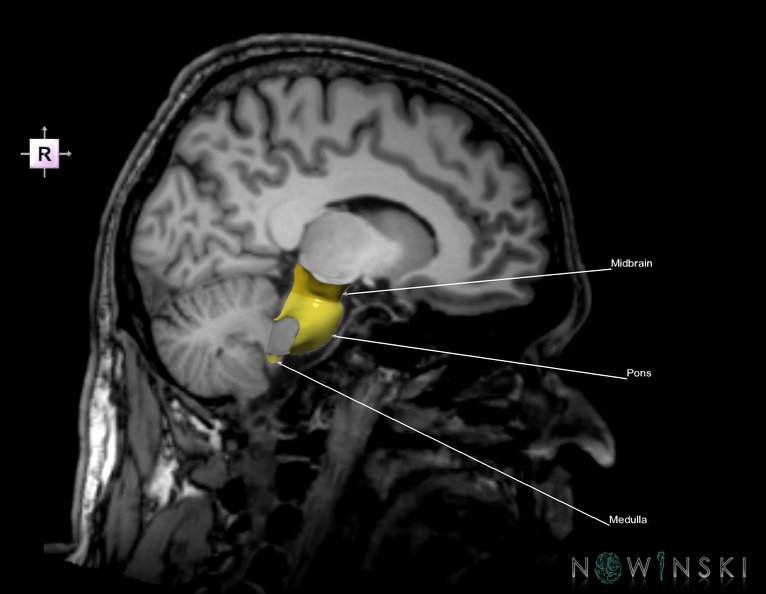

G6.T9.4.V4.P-10S.Brainstem–Triplanar

G6T9.4.Brainstem–Triplanar